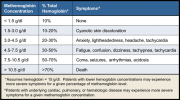

| 07:47, 3 ביולי 2017 | מטהמוגלובין4.png (קובץ) |  |

129 קילו־בייטים | Motyk | 1 | |